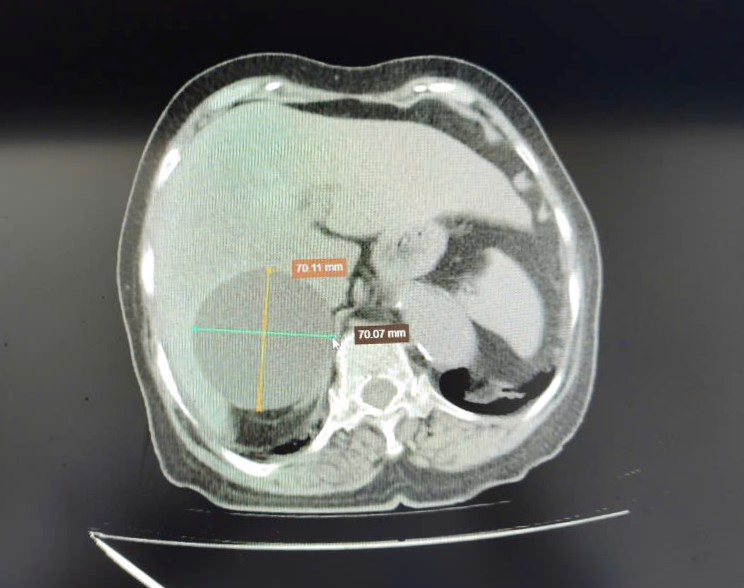

Hình ảnh phim chụp CT ổ bụng người bệnh cho thấy nang gan kích thước lớn

Đáng chú ý, hình ảnh chụp CT ổ bụng ghi nhận nang gan kích thước lớn khoảng 70,11 mm x 70,7 mm gây đau tức vùng thượng vị, chèn ép các cơ quan lân cận, ảnh hưởng đến sức khỏe và chất lượng cuộc sống của người bệnh.